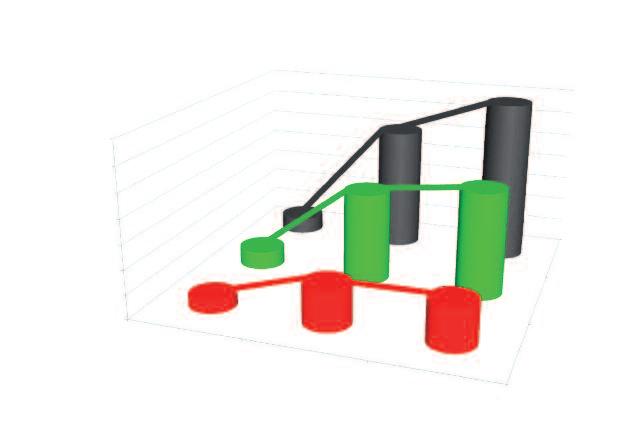

Demistificazione del cancro tramite le statistiche dell’OGM (Organizzazione Mondiale della Sanità)

Altre malattie

Malattie cardiocircolatorie

A. Ogni anno muoiono di cancro 7,5 milioni di persone

Altre malattie Infezioni Infezioni

Malattie cardiocircolatorie

B. Solo in Nord America e in Europa ogni anno muoiono di cancro 5,6 milioni di persone